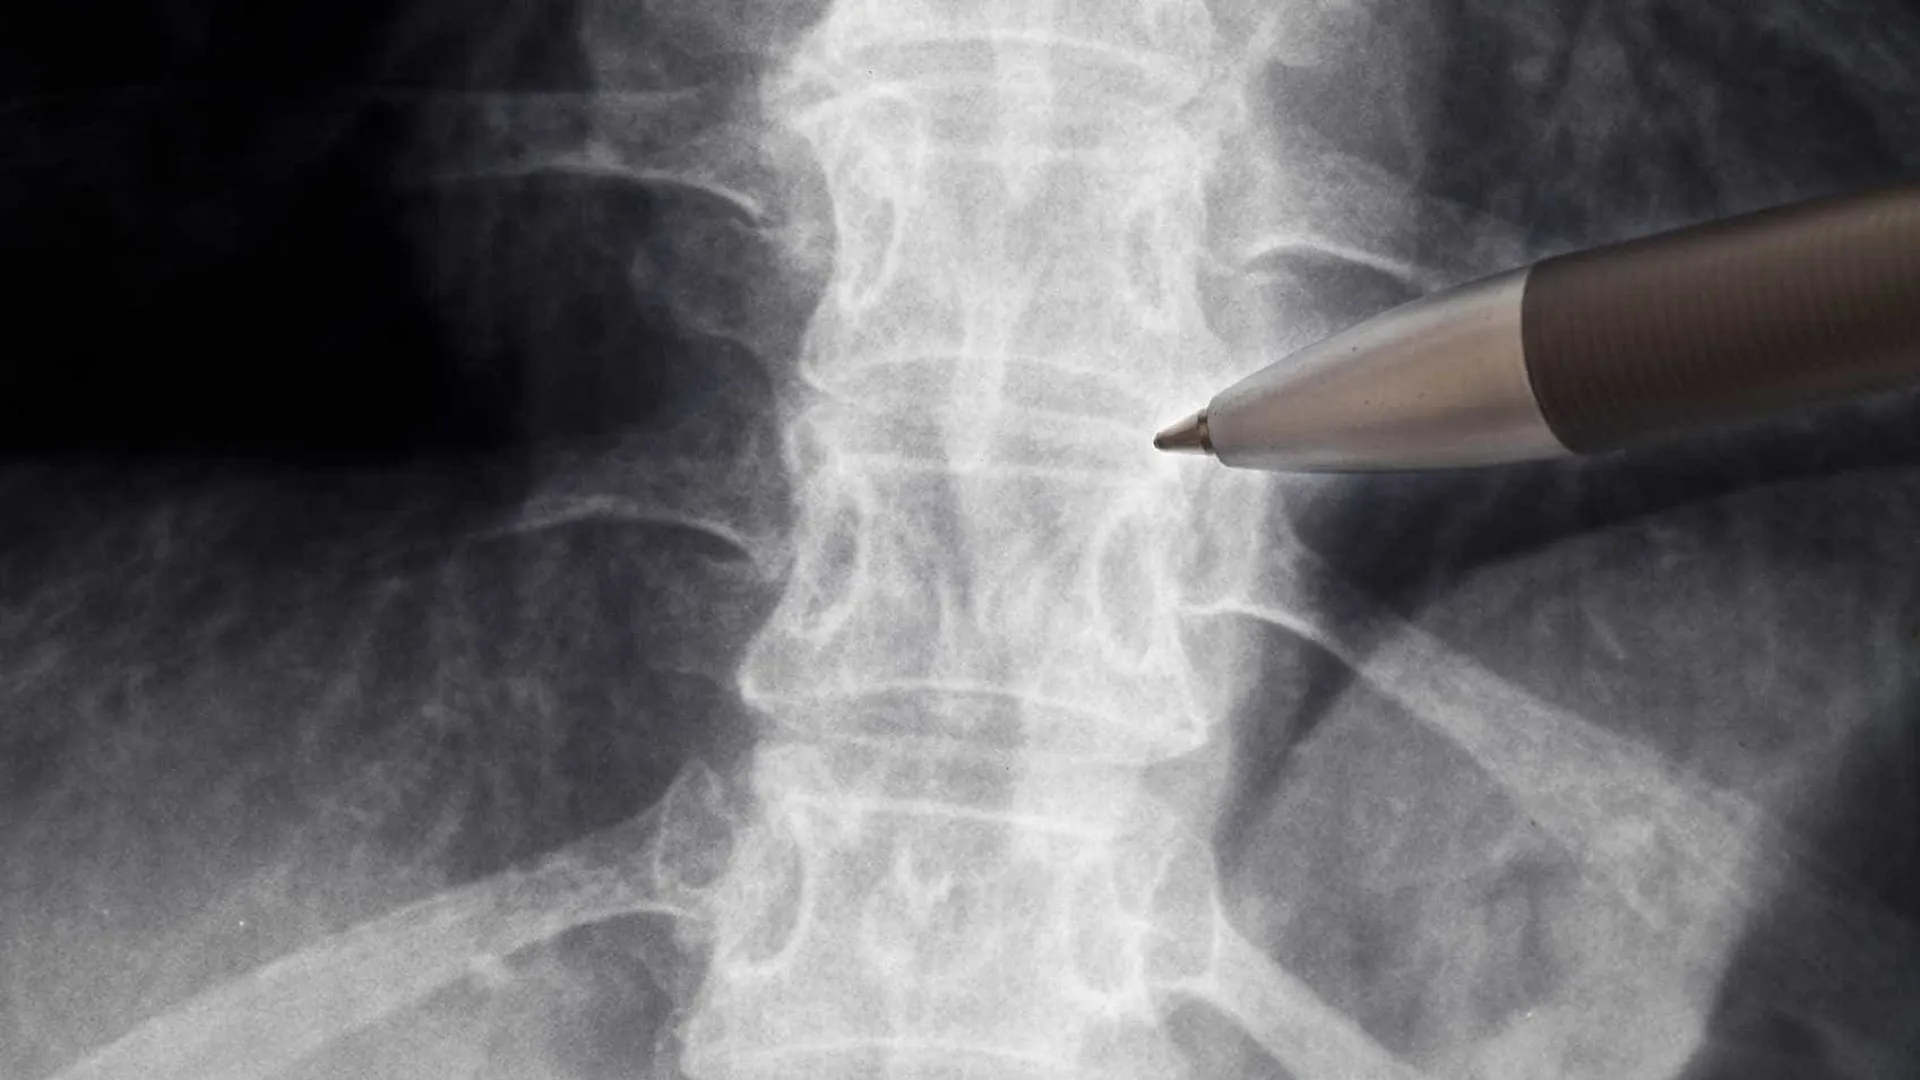

Neurologistas alertam para falta de evidências sobre ação da polilaminina em lesão medular

SÃO PAULO, SP (FOLHAPRESS) – A ABN (Academia Brasileira de Neurologia) divulgou nesta segunda-feira (23) uma nota em que reforça a inexistência de…